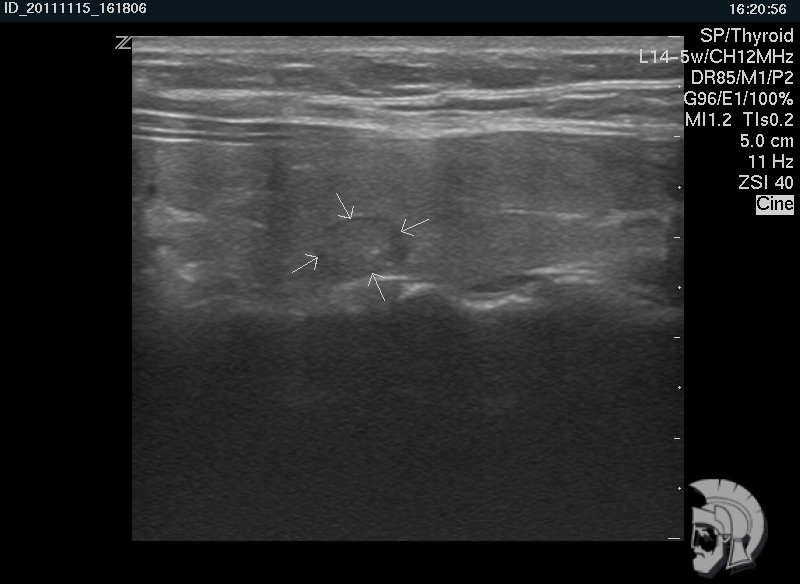

| Фото правостороннего узлового зоба у мужчины 28 лет. Узел в задних отделах правой доли указан стрелками |

| Фото правостороннего узлового зоба. Тот же случай |